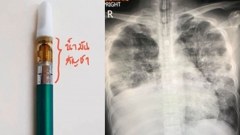

พบอีก! รพ.กรุงเทพ ยอมรับมีผู้ป่วยโควิด 19 หลังผู้ป่วยเข้ามารับการผ่าตัดเพราะอุบัติเหตุ แต่กลับพบว่าติดเชื้อ